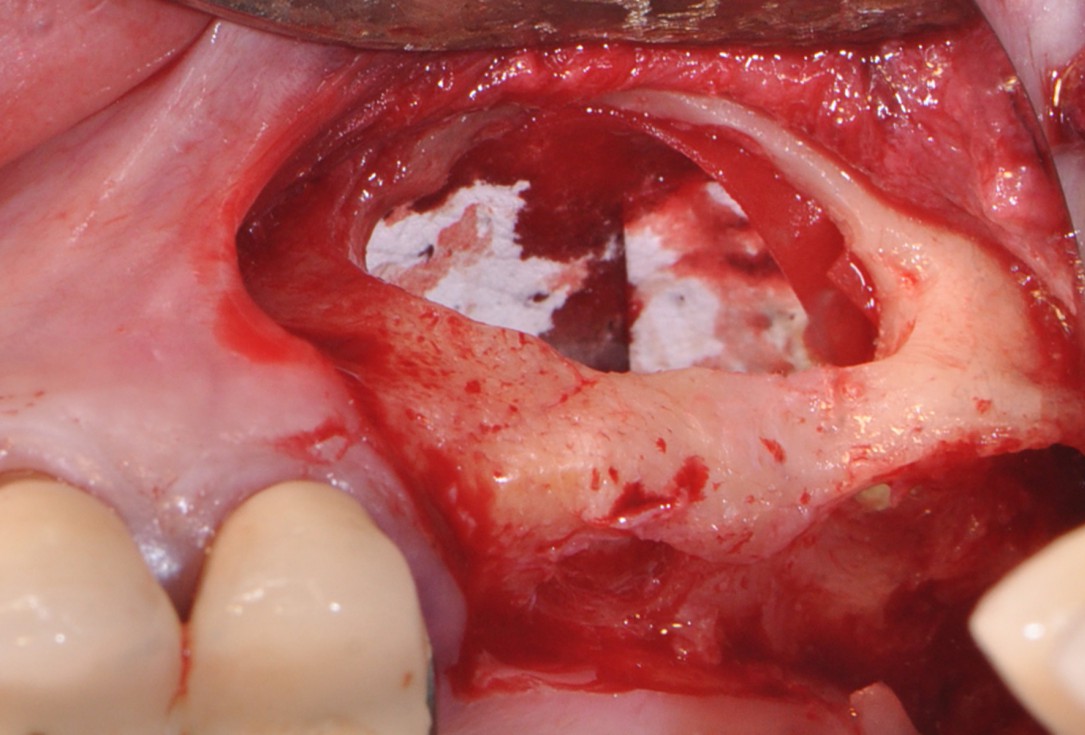

8/16 - Filling subantral cavity with cerabone® 1.0 -2.0 mm particle size

One-stage sinus lift - Dr. V. Kalenchuk

9/16 - Covering the augmentation site with collprotect® membrane

One-stage sinus lift - Dr. V. Kalenchuk